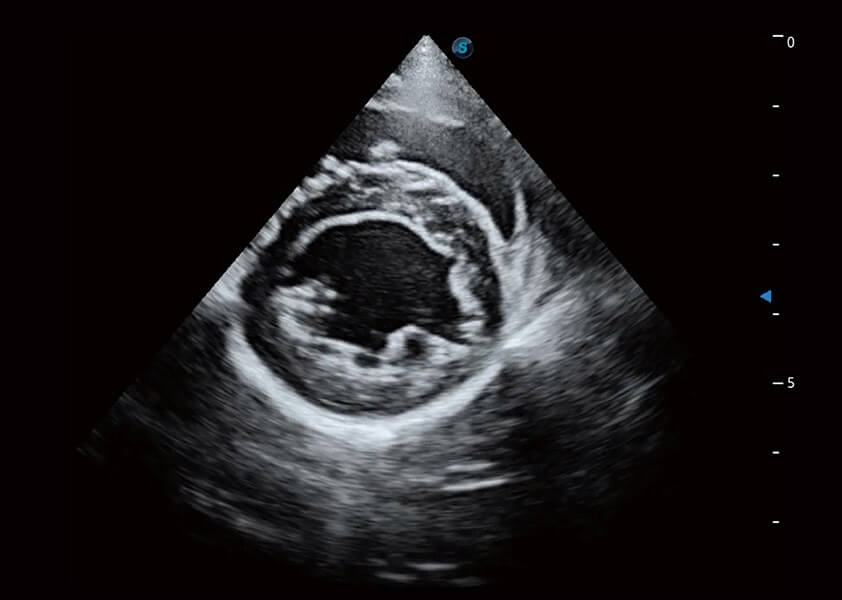

ProPet 60 作为一款高端台式动物超声设备,为动物医生的日常诊断提供了一系列贴合动物临床需求、解决临床实际问题的高级成像功能。凭借全系列高清探头,满足医生对腹部、心脏、生殖、浅表、肌骨等成像的所有需求,切实帮助您提升检查效率,提高诊断信心。

动物是人类最亲密的朋友和最值得信赖的伙伴。诸侯快讯官网也一直致力于探索动物专用的超声影像解决方案。 全新推出的ProPet系列,是诸侯快讯官网在动物超声影像智能化、专业化、精准化的一次跨越式革新。动物不能用言语来表述自己的不适,通过超声影像,ProPet系列搭建了动物医生与不同物种沟通的“桥梁”,为动物医生注入了“治愈之力”。